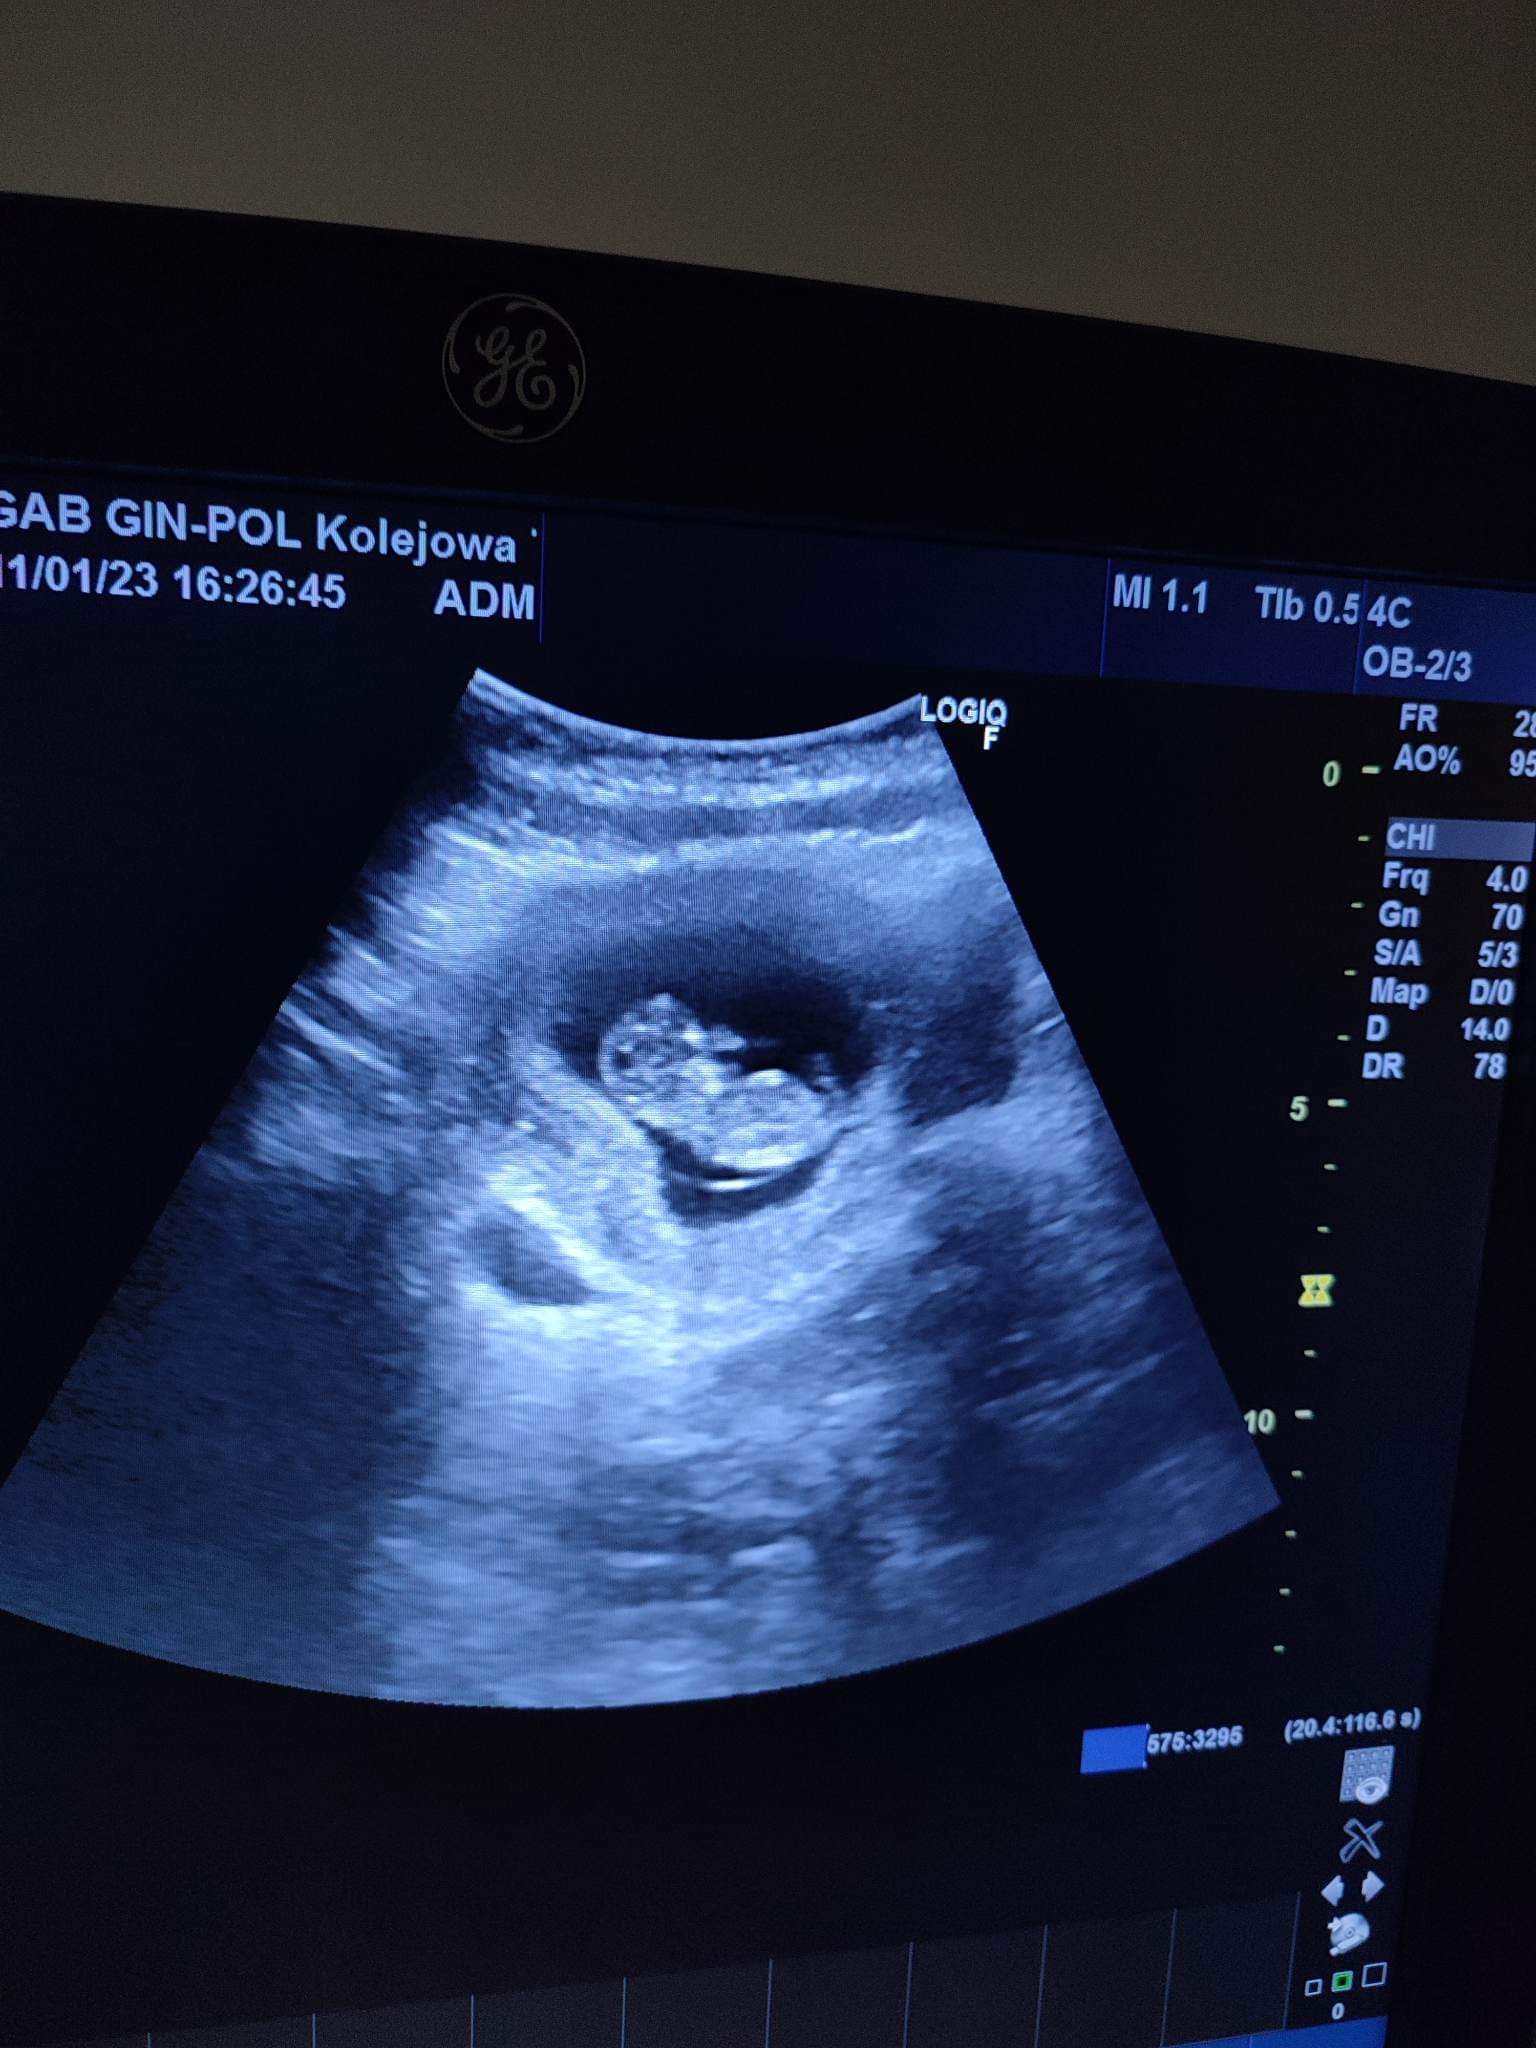

Załączniki

• received_536066788481375.jpeg

received_536066788481375.jpeg

193,4 KB · Wyświetleń: 132